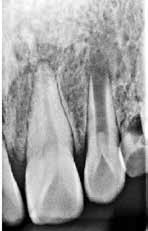

Fig. 2. Tidligere behandlet tand med insufficient eller helt manglende rodfyldning i kanalerne. A. Præmolarer i overkæben med tre insufficiente rodfyldninger og efterfølgende restaurering med stiftopbygning og krone. Desuden første molar uden synlig rodfyldning, men med restaurering, der inddrager pulpakammeret. B. Første molar i overkæben, som kun har synlig rodfyldning i den palatinale kanal. C. Insufficient rodfyldning eller overset rodkanal i første molar i overkæben.

Fig. 2. Previously treated tooth with no or inadequate root filling in canals. A. Maxillary premolars with 3 roots inadequately filled and restored with post and crown. Maxillary first molar with no visible root filling with restoration in pulp chamber and coronal restoration. B. Maxillary first molar with visible root filling only in the palatal canal. C. Inadequate root filling or missed root canal in maxillary first molar.

peroperative faktorer. En af dem er manglende behandling af en rodkanal, enten fordi den ikke blev fundet, eller fordi tandlægen ikke ledte efter den (Fig. 2A-C) (8,9). Det er påvist, at apikal parodontitis forekommer hyppigere i tænder med mindst én ubehandlet eller overset rodkanal (10). Accidentelle perforationer fører ofte til ekstraktion af tanden, men kan almindeligvis undgås med fornuftige endodontiske arbejdsgange (11). Ufuldstændig instrumentering eller forsegling af rodkanalen enten som følge af forkert rodmål eller på grund af fx instrumentfraktur, hyldedannelse eller overinstrumentering af den apikale konstriktion kan føre til, at infektionen persisterer. Rodfile kan frakturere som følge af cyklisk træthedsbrud eller vridningsbelastningsbrud, og incidensraten for brud ligger på 1 % (12). Det sted i tandsættet, der oftest giver anledning til instrumentfraktur, er den apikale del af en mesiofacial rodkanal i en molar (Fig. 3). Kraftig afbøjning af kanalen forøger risikoen for, at filen frakturerer (13). En for kort rodfyldning (> 2 mm fra radiologisk apex) har ligesom overfyldning med guttaperka en nedsat succesrate (14).